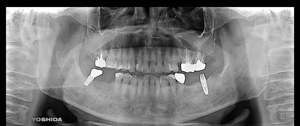

@S.Y‚³‚ñ@ 65Π @’j«@Ž©‰c@@Žèp“ú@‚Q‚O‚O‚W”N@‚UŒŽ‚P‚V“úi‰Îj  ㉺Š{ƒm[ƒxƒ‹ƒKƒCƒhŽg—p@Ö¬“à’ÁÖ@•¹—p

@@@ ㉺Š{  All on ‚U@‘¦Žž‰×d

@    @Rpl Tapered Rp ‚P‚O mm(‚V–{)  @ Rpl Tapered Rp  ‚P‚R mm(‚T–{)@